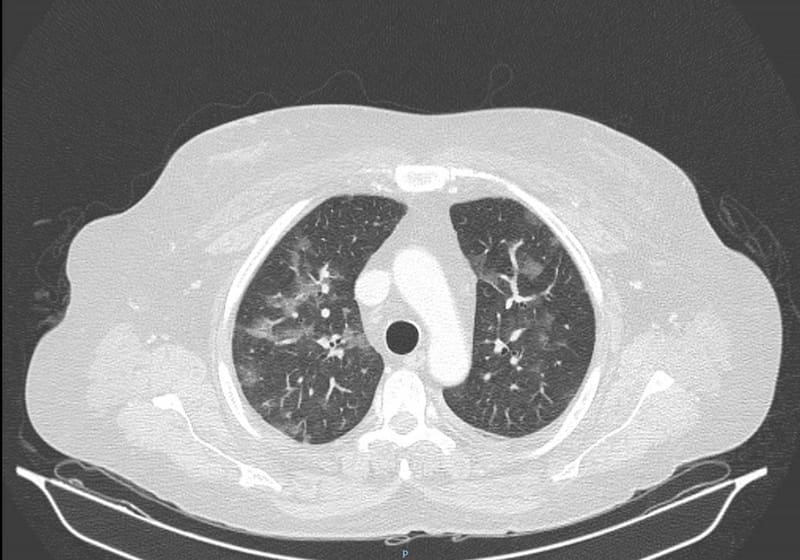

"Sin embargo, hay algunos pacientes en que esta inflamación puede evolucionar hacia fibrosis, donde se produce una cicatriz, y esa zona del pulmón se empieza a retraer, el tejido normal del pulmón se reemplaza por tejido fibroso cicatrizado. Eso puedo dejar un daño secuelar respiratorio”, explica Reid.

“Ese daño si es fibrótico, puede dejar una secuela para siempre. Disminuye la capacidad respiratoria de la persona. No ocurre en todos los pacientes, solo en un cierto porcentaje que desarrollan esta fibrosis. Son pocos casos, generalmente los más graves. Pacientes que caen en ventilación mecánica por períodos largos, con cuadros más severos. Aunque es súper variable el daño en cada persona", señala Reid.

Sin embargo, este daño no implica que esta persona sea más vulnerable a futuras enfermedades. “Más bien hay que mirarlo como una secuela. Queda con una disminución de su reserva pulmonar. No se va a enfermar más fácil, pero si lo hace y agarra otra neumonía, evidentemente partirá de una basal más baja”, explica el broncopulmonar de Clínica Universidad de los Andes.